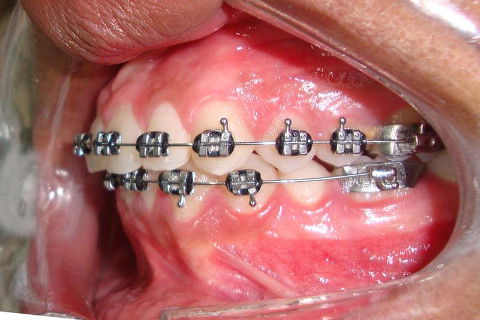

Paciente D. F. S., 19 anos, com queixa principal o apinhamento superior e inferior. Realizado o diagnóstico foi proposto duas opções de tratamento: exodontia de 04 pré-molares ou exodontia de incisivo inferior e slices superior, verticalização do molar 47 para futura instalação de implante do 46.

O tratameno foi iniciado com a montagem completa do aparelho superior e inferior, a indicação da exodontia do elemento 41, alinhamento e nivelamento.

Atualmente estamos com  04 meses de tratamento, podemos notar uma grande evolução no caso em pouco tempo.

Posteriormente, iremos realizar a verticalização do 47 com alça de verticalização e publicarei novas fotos.